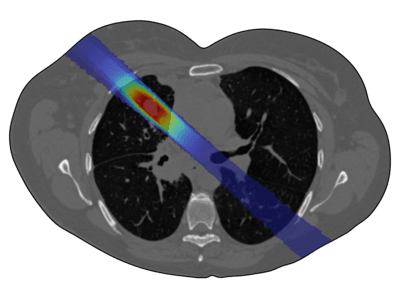

Radiation therapy is a key cancer treatment, used in over 50% of cases, either as a standalone or in combination with surgery and chemotherapy. It involves delivering ionizing radiation to damage cancer cell DNA, preventing their proliferation. Conventional radiotherapy mainly employs X ... 詳細を見る